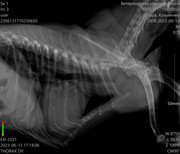

Коллапс трахеи форум